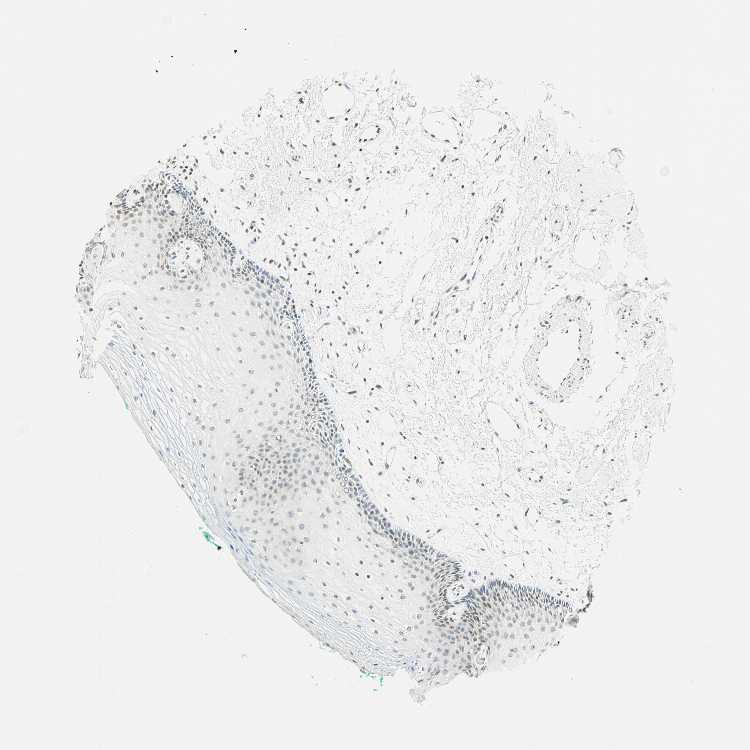

TISSUE PRIMARY DATA ORAL MUCOSA Show tissue menu

ORAL MUCOSA - Antibody stainingi

Antibody staining in the annotated cell types in the current human tissue is reported as not detected, low, medium, or high, based on conventional immunohistochemistry profiling in selected tissues. This score is based on the combination of the staining intensity and fraction of stained cells.

Each image is clickable and will lead to virtual microscopy that enables deeper exploration of all samples and also displays staining intensity scores, fraction scores and subcellular localization as well as patient and tissue information for each sample.

Antibody CAB009572Antibody CAB070867Antibody CAB080131

Squamous epithelial cells MediumHighHigh